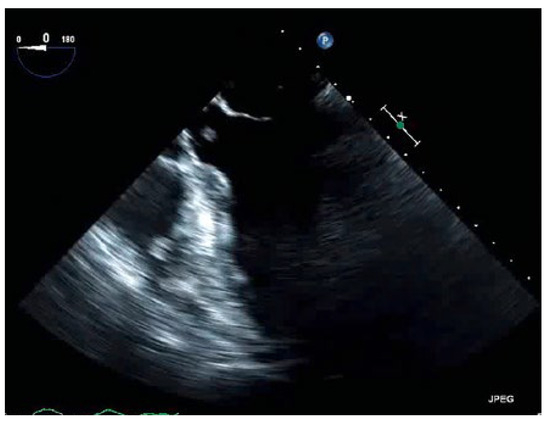

Thrombus in Transit

An 88-year-old man with a history of transient ischaemic attack, chronic kidney disease and primary hypertension presented with dyspnoea and was found to have large bilateral pulmonary emboli on a computedtomography angiogram of the chest [...]